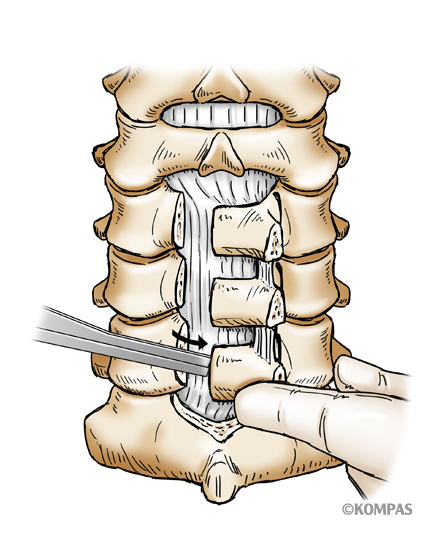

頚椎前方除圧固定術

適応となる疾患:頚椎椎間板ヘルニア、頚椎症性神経根症など

頚部の前方より切開し椎間板や骨の出っ張りを切除し、神経の圧迫を解除します。最近は、椎間板や骨を切除した部分に、椎体間ケージと呼ばれる箱型の金属を使用することで、腰骨からの採骨が不要となり手術時間が短縮できます。また、術後の採骨部痛(骨をとる部分の痛み)を防ぐことができます。手術時間は1時間~1時間30分ぐらいで、翌日から歩行が許可されます。入院期間は通常10~14日間ぐらいになります。